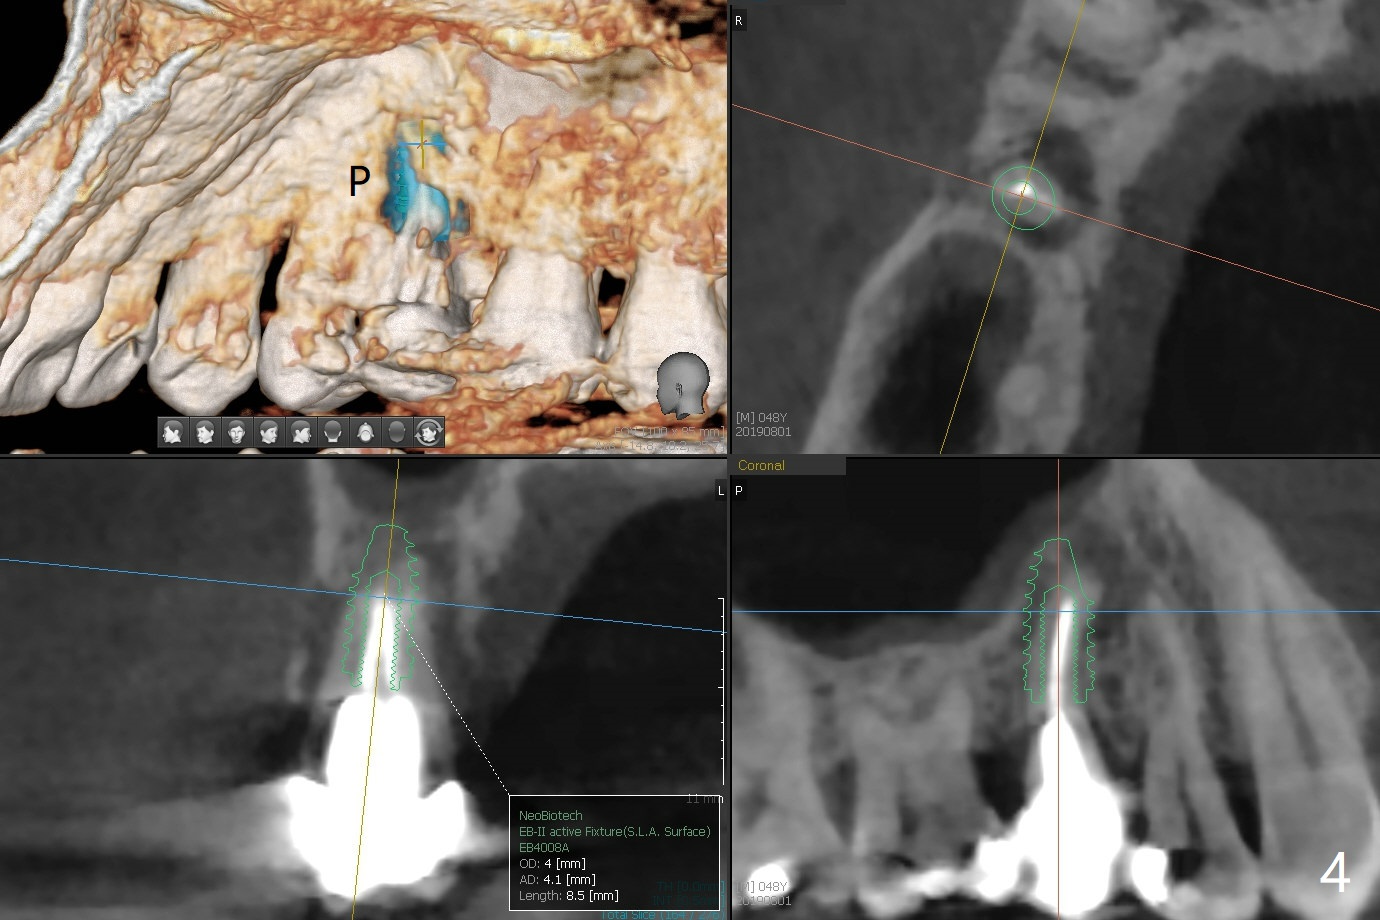

A 48-year-old man has had palatal and buccal abscesses at #4 for 6 and 1 months, respectively (Fig.1). The patient loves bubble gums. There is a post at #4 (Fig.2). CBCT shows apical buccal and palatal defects (Fig.3,4). There are no deep periodontal pockets. The tooth has mobility II. No guide is fabricated so that we have options to do bone graft or immediate implant after extraction, depending on extent of bone defects. Later impression is taken for guide. Use UF implant 4.5x10 mm with sinus lift (PRF membranesx2).